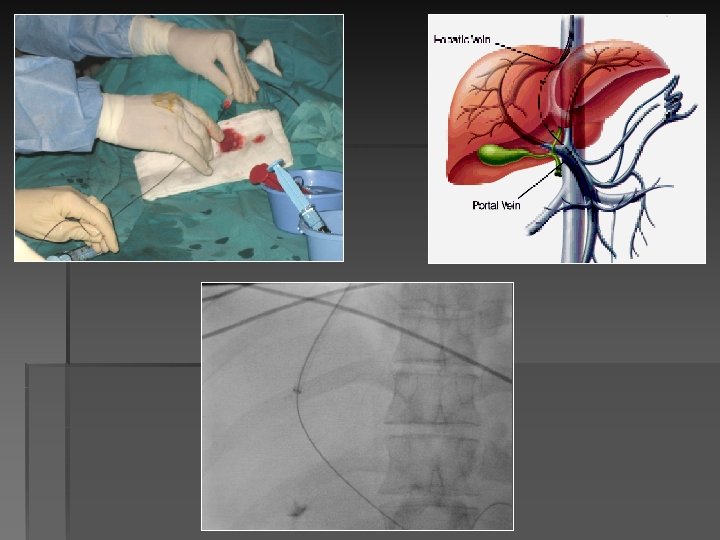

-Guía rígida por catéter multipropósito, avanzar introductor 10 F a porción media vena hepática.

-Guía rígida por catéter multipropósito, avanzar introductor 10 F a porción media vena hepática. -Realizar punción transhepática.

-Se pueden emplear como guía para la punción intrahepática la ecografía o la flebografía

-Se pueden emplear como guía para la punción intrahepática la ecografía o la flebografía hepática oclusiva con CO 2. -Ecografía requiere experiencia. -Flebografía con CO 2 método de mayor aceptación en la acualidad. El CO 2 pasa de forma retrógrada a sistema portal. Permite obtener buen mapa portal.